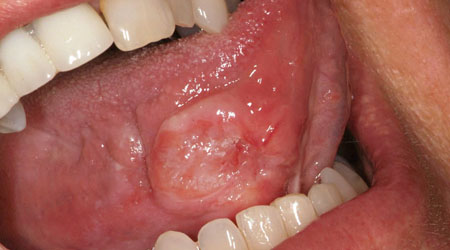

See your dentist if you suspect you have gum disease because the sooner you treat it the better. The early stage of gum disease is called gingivitis. If you have gingivitis, your gums may become red, swollen and bleed easily. At this stage, the disease is still reversible and can usually be eliminated by a professional cleaning at your dental office, followed by daily brushing and flossing.

Advanced gum disease is called periodontitis. Chronic periodontitis affects 47.2% of adults over 30 in the United States. It can lead to the loss of tissue and bone that support the teeth and it may become more severe over time. If it does, your teeth will feel loose and start moving around in your mouth. This is the most common form of periodontitis in adults but can occur at any age. It usually gets worse slowly, but there can be periods of rapid progression.

Aggressive periodontitis is a highly destructive form of periodontal disease that occurs in patients who are otherwise healthy. Common features include rapid loss of tissue and bone and may occur in some areas of the mouth, or in the entire mouth.